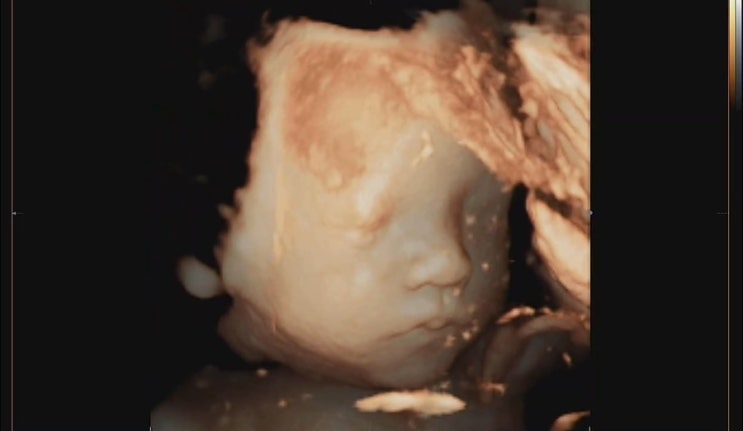

임신/출산) 31주차 입체초음파 도전!

31주차 2일이 되던 날. 드디어 신혼집으로 복귀했어요! 30주 이후부터는 2-3주에 한번씩 정기검진이 있다는...